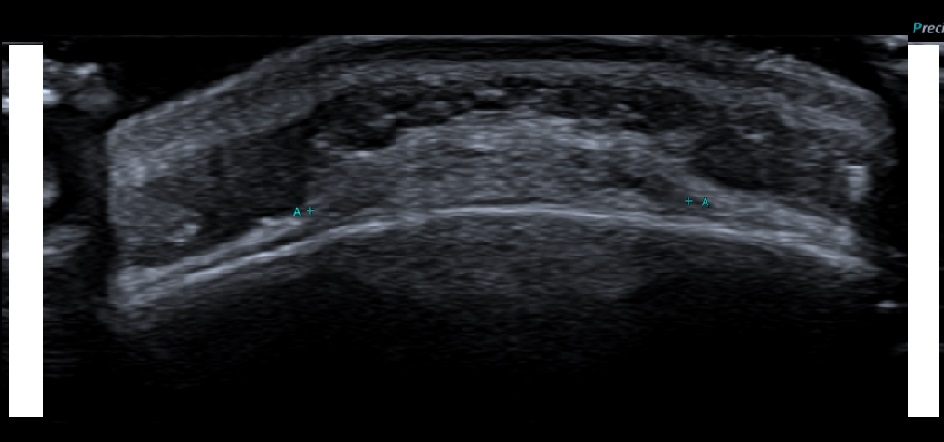

Forehead lump, mobile, soft and fluctuant, persistent for more than 1 year.

Solid echogenic mass between the periosteum and galea aponeurosis. It has a relatively flat base and smooth convex displacement of galea aponeurosis. No vascularity. Underlying bony cortex is smooth.

Subgaleal lipoma.